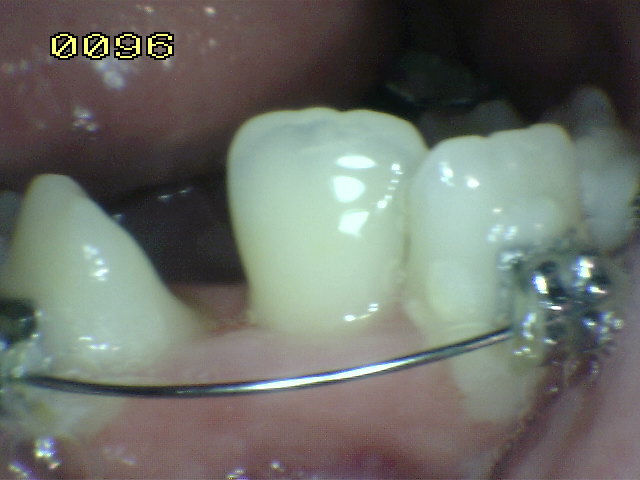

Control del distalamiento de canino